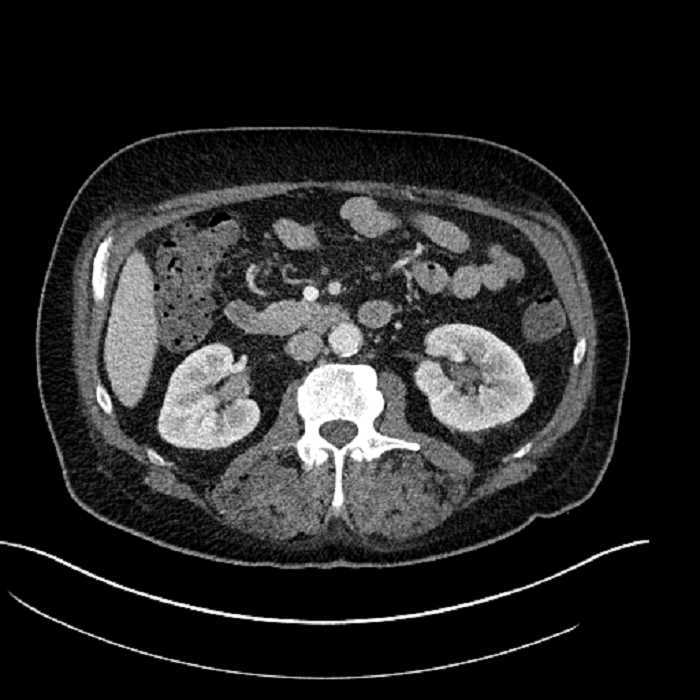

Age: 63

Sex: Male

Indication: Abdominal pain

• Large fluid density structure in hepatic segments 7 and 8 measuring 10 x 7 x 7 cm with internal septation and circumferential ill-defined low density compatible with edema

• Peripherally enhancing subcapsular collections along the anterior margin of the left hepatic lobe measuring 3 x 1 cm and 2 x 1 cm

• Clearly marginated fluid density structure in segment 7 and several other scattered tiny hypodensities, which likely represent cysts

• Hepatic abscess

Acute sigmoid diverticulitis complicated by a small contained perforation and a large abscess in the right hepatic lobe. Additional small subcapsular abscesses along the anterior margin of the left hepatic lobe.

Additionally, loss of the normal fat plane between the peridiverticular collection and adjacent thickened loops of small bowel raises the potential for an enterocolonic fistula.

• The classic CT imaging appearance is a double target sign with internal low density surrounded by an internal enhancing rim (capsule) and a low density external rim (edema)

Hepatic abscess showing the double target sign with low density internally surrounded by a thin inner enhancing rim (red arrow) and ill-defined outer low density rim (yellow arrow). Blue arrow indicates an internal septation. Red arrows: additional smaller subcapsular abscesses. Red arrow: focal contained perforation associated with diverticulitis.